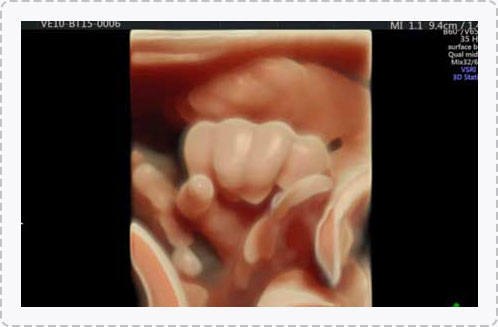

四维彩超能够直观、立体地显示人体器官的三维结构以及动态,实时地观察立体结构,被广泛用于检查胎儿发育状况,立体观察胎儿在子宫内发育情况的同时,还能够清晰显示胎儿在子宫内的动态,让准爸妈们一起观看宝宝在妈妈肚子里的动作、神态,还可将这个过程制作成光碟保存,让宝宝能够拥有完整的0岁相册,留下珍贵的纪念。

宝宝的0岁写真,是值得每个父母珍藏的。